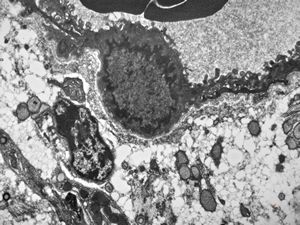

M,29y. | jejunum - lipid malabsorption

jejunum … lipid malabsorption